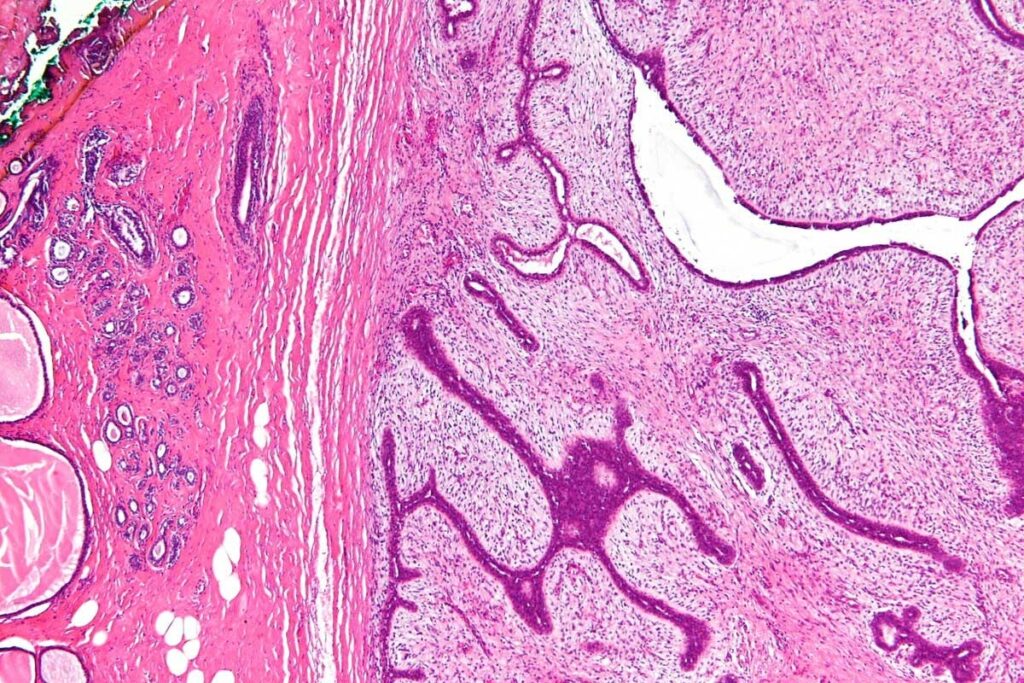

A biopsy is essential for diagnosing muscle tissue tumors. It takes a tumor sample for examination. There are needle biopsy and surgical biopsy methods, each with its own use.

The biopsy tells if the tumor is cancerous and its type and grade. This info is key for treatment planning.